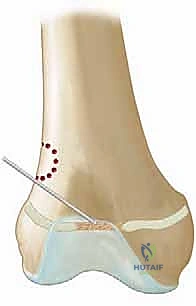

الخطوة الأولى: التخطيط والوصول الجراحي

بناءً على خريطة الرنين المغناطيسي، يتم تحديد موقع الشق الجراحي بدقة. إذا كان العائق طرفياً (محيطياً)، يتم الوصول إليه مباشرة. أما إذا كان مركزياً (في وسط العظم)، يتم عمل نافذة عظمية صغيرة في الكردوس (Metaphysis) للوصول إليه دون الإضرار بالغضروف السليم المحيط.